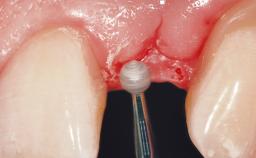

Immediate Flapless Placement of an Implant in a Maxillary Right Lateral Incisor Site

This 43-year-old male patient, a non-smoker, came to our practice because of a fracture of tooth 12 caused by a bicycle accident. Due to the combined para- and infrabony crown and root fracture, tooth extraction, and subsequent implant placement were suggested to the patient as the therapy of choice. The patient had high esthetic expectations with regard to the treatment outcome and asked for an immediate fixed provisional restoration. His individual esthetic risk profile summed up to a medium esthetic risk.

Placement Protocol Immediate implant placement